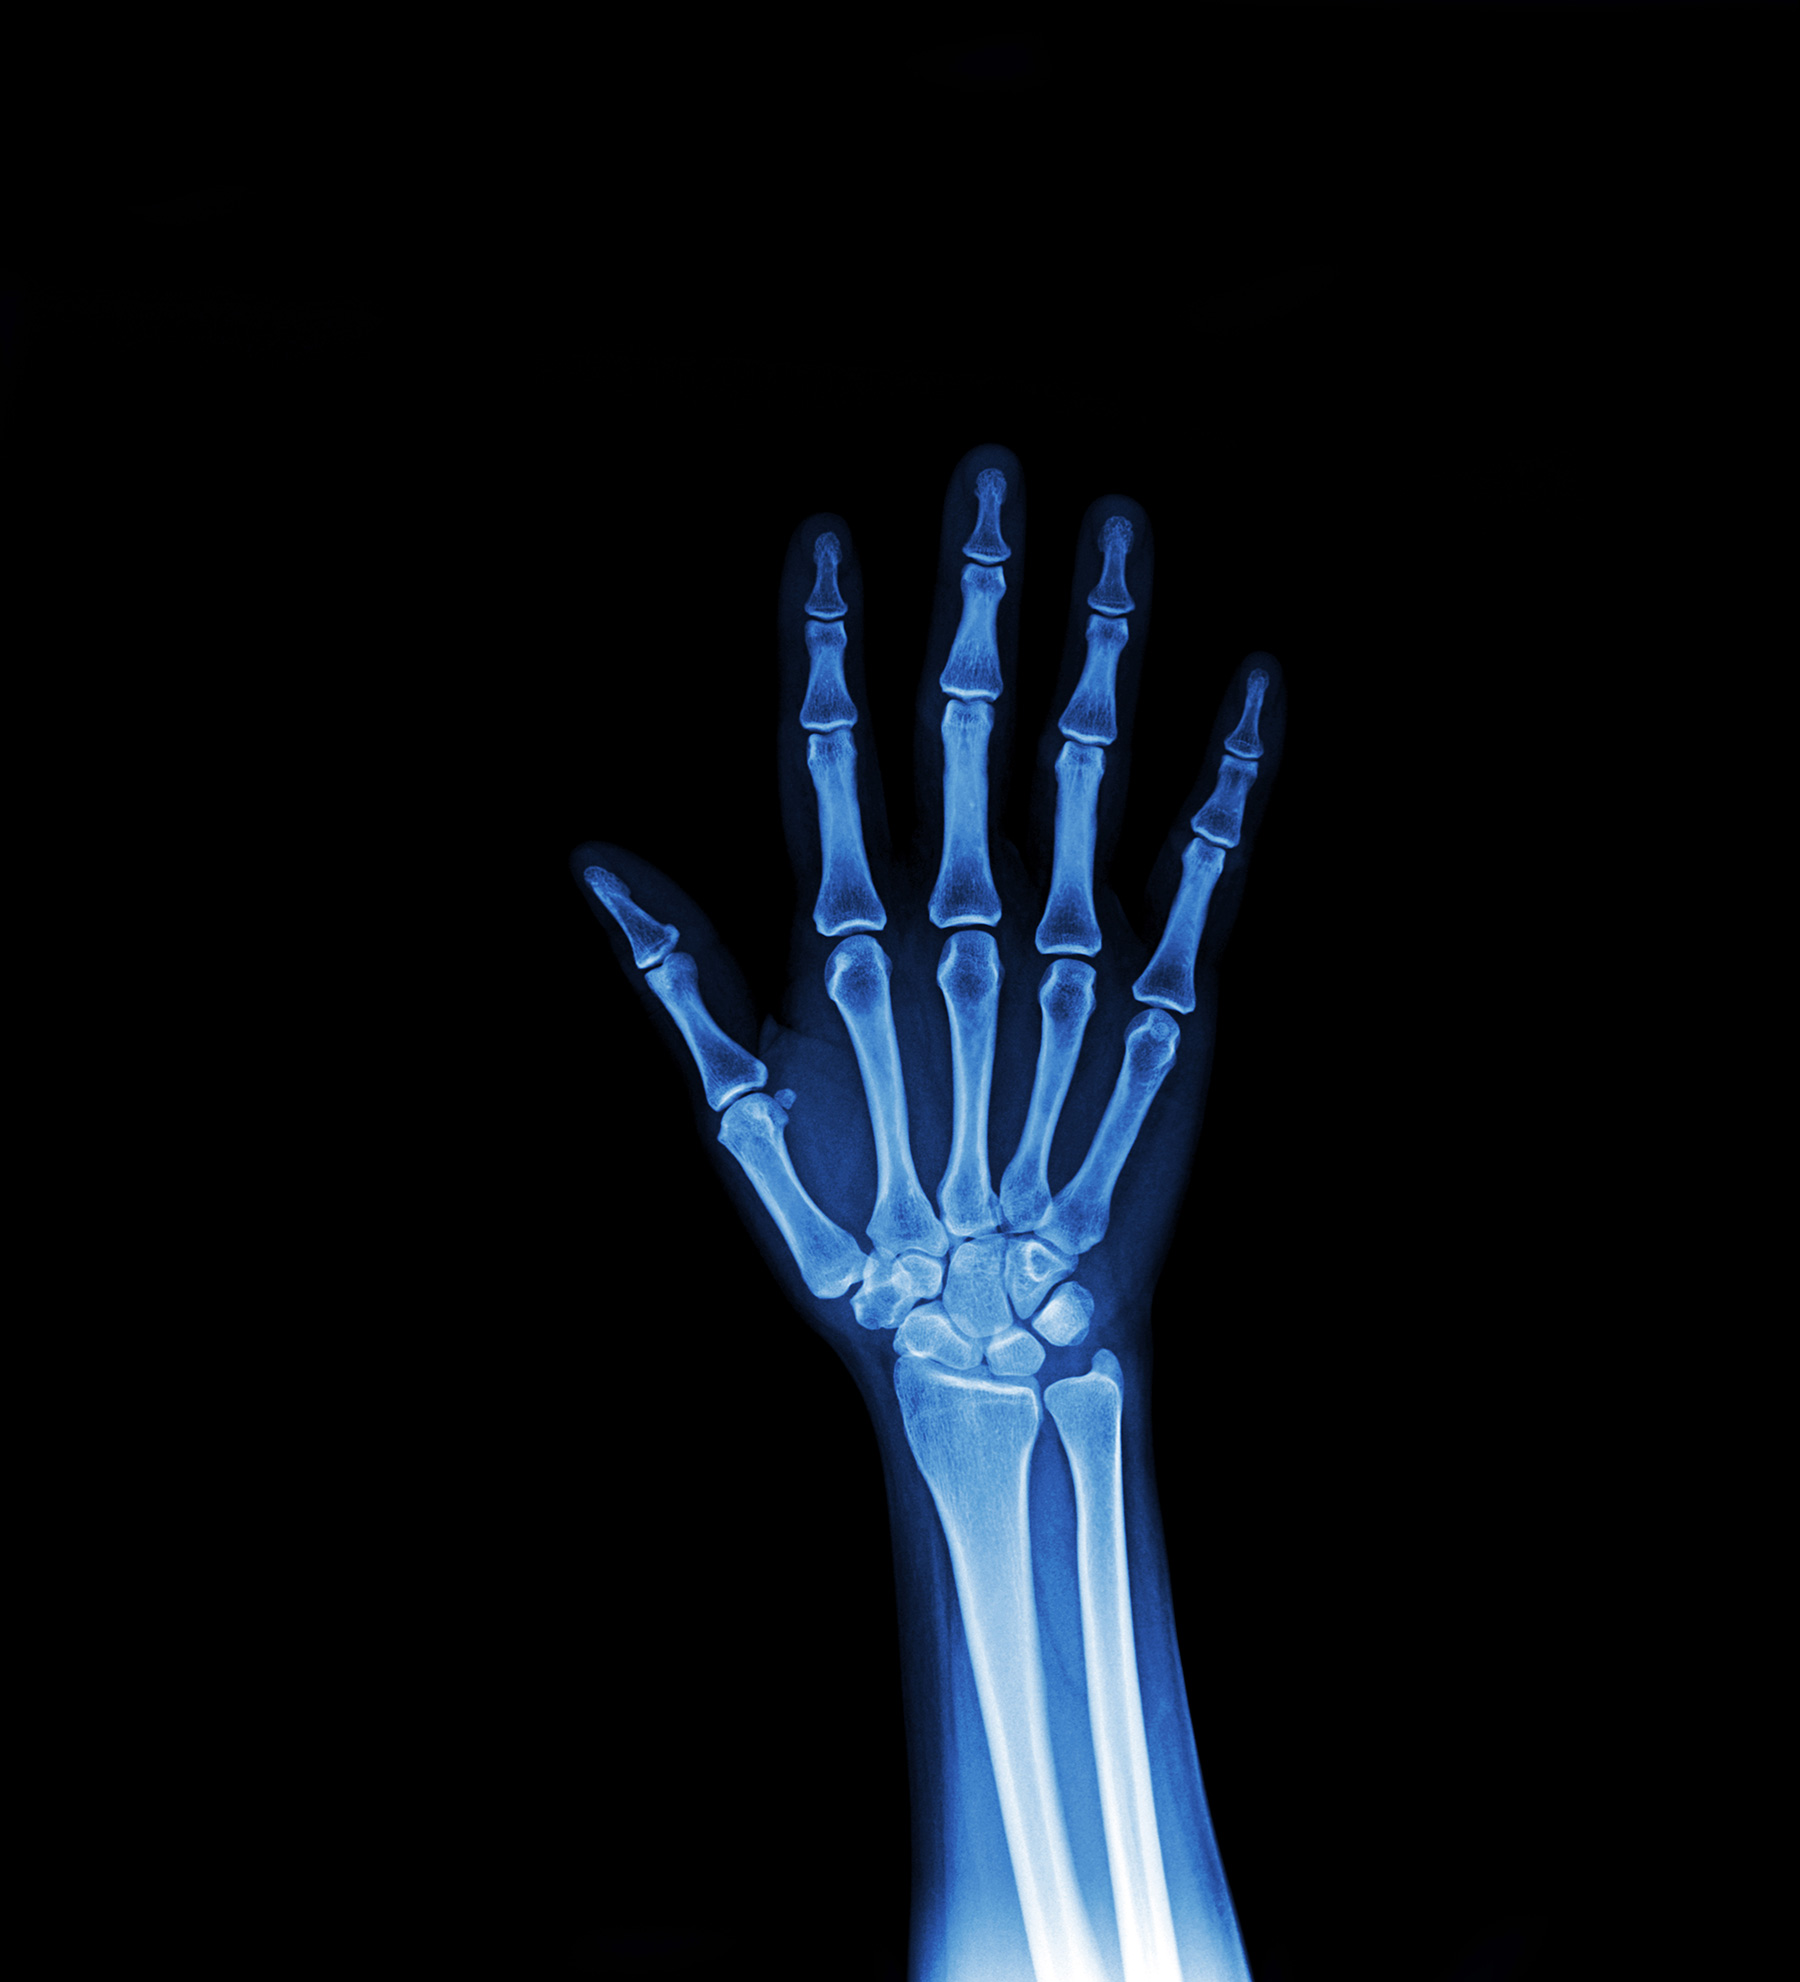

Extremities (Hand, Wrist, Leg, Foot)

From sports injuries to accidental falls, X-rays of the extremities are vital for orthopedics. We provide high-quality AP (Anteroposterior) and Lateral views for hands, wrists, arms, legs, and feet.

Our digital sensors provide exceptional detail of the trabecular bone pattern, allowing for the detection of fractures, dislocations, and bone infections (osteomyelitis). We also assess bone age in children to monitor growth disorders.

Whether it is a "Left hand AP View" or a complex foot fracture, our technicians ensure precise positioning for the most diagnostic image.

Key Highlights

• Immediate fracture detection.

• Assessment of Joint Dislocations.

• Bone Age estimation for Pediatrics.

• Evaluation of foreign bodies (glass/metal).